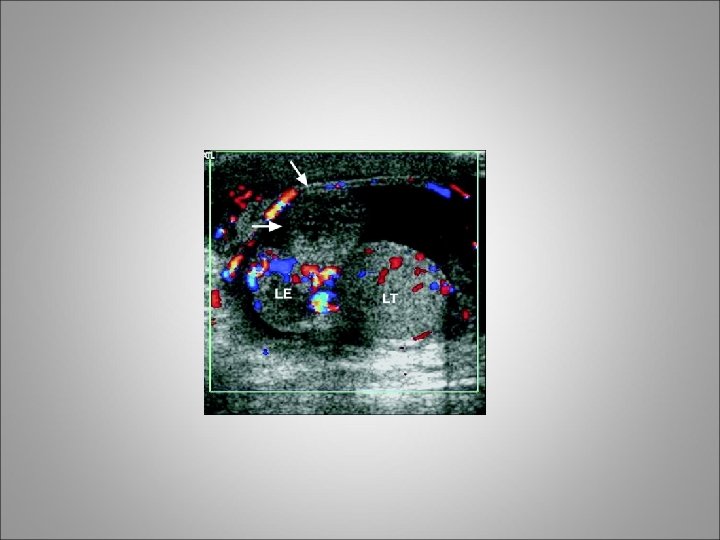

Testicular Trauma • Testicular rupture or fractured testis refers to a rip or tear in the tunica albuginea resulting in extrusion of the testicular contents • Blunt trauma accounts for approximately 85% of cases, and penetrating trauma accounts for 15% • As many as 80% of hematoceles (blood in the tunica vaginalis) are associated with testicular rupture

Clinical diagnosis • Patients typically present to ER with a straightforward history of injury • Symptoms include extreme scrotal pain, frequently associated with nausea and vomiting • Physical examination often reveals a swollen, severely tender testicle with a visible hematoma • Scrotal or perineal ecchymosis may be present • When evaluating a patient with a clinical history of only minor trauma, do not overlook the possibility of testicular torsion or epididymitis

Clinical diagnosis • For penetrating injuries, determine the entrance and exit sites of the wound. • Screening urinalysis is important to rule out urinary tract infection or epididymo-orchitis • Scrotal ultrasound imaging with Doppler studies is valuable for diagnosing and staging testicular injuries • The presence of a disrupted tunica albuginea is pathognomonic for testicular rupture

Indications for scrotal exploration • Uncertainty in diagnosis after appropriate clinical and radiographic evaluations • Disruption of the tunica albuginea • Large hematocele • Absence of blood flow on scrotal ultrasound images with Doppler studies

scrotal exploration • Clinical hematoceles that are expanding or of considerable size (eg, 5 cm or larger) should be explored • Collections of smaller size are also often explored, because it has been shown that such practice allows for more optimal pain control and shorter hospital stays • If the testis is fractured, testicular debridement and surgical closure of the tunica albuginea are necessary